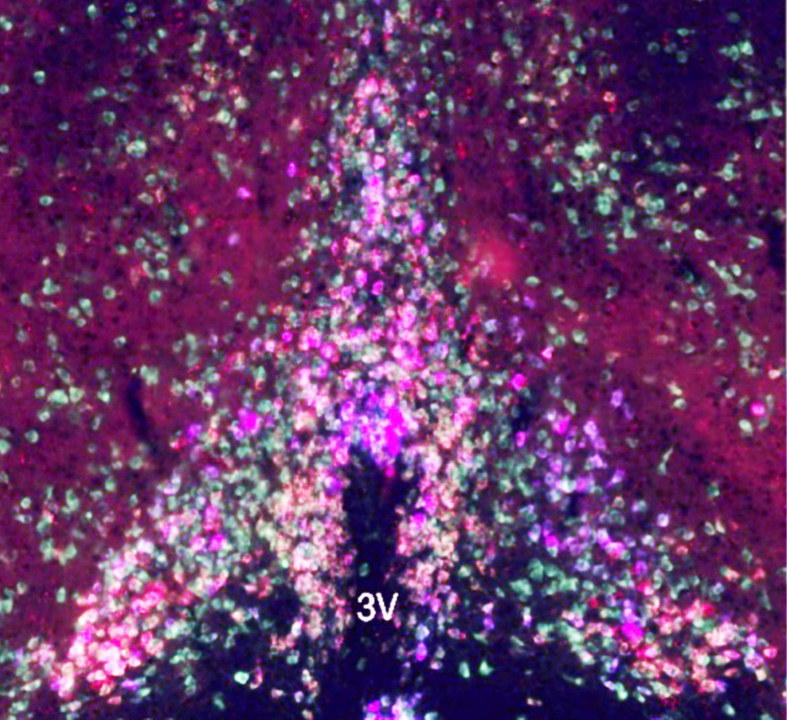

Suprachiasmatic nucleus in the human brain stained immunohistchemically for vasoactive intestinal peptide (VIP).  The amplitude of circadian rhythms in older people is proportional to the number of surviving VIP neurons in the SCN (Wang et al., Ann Neurol 215;78:317). The human SCN controls all aspects of circadian physiology and behavior, but is only 0.5 mm across in a human brain.  Scale = 1.0 mm on left, 0.1 mm on right.